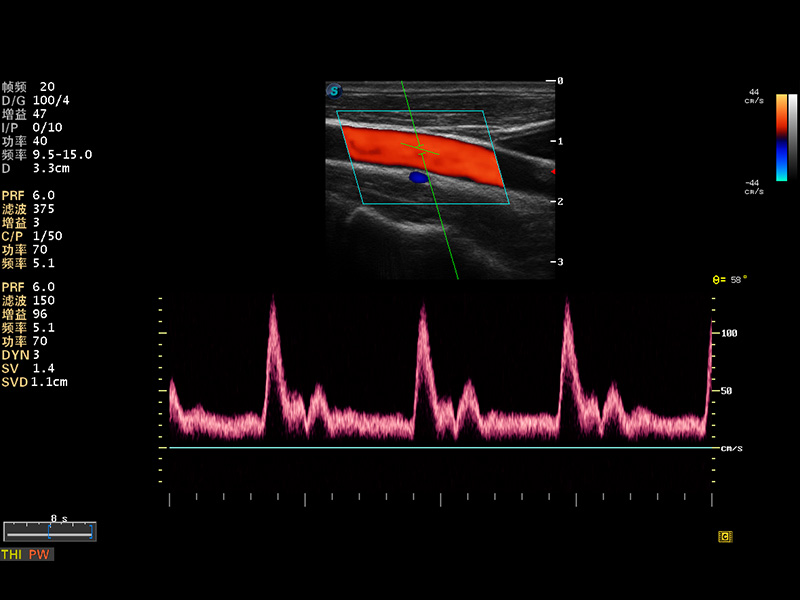

S8 EXP便携式彩色多普勒超声诊断仪是美狮贵宾会官网研发的高端全身应用型便携彩超。高通道的VIS平台融合可视化(Visual)、智能化(Intelligent)和人性化(Smart)的特点,配以美狮贵宾会官网自主研发生产的探头大家族,使您能够快速、准确的获得病人信息,提高工作效率的同时减轻疲劳。

多波束形成器